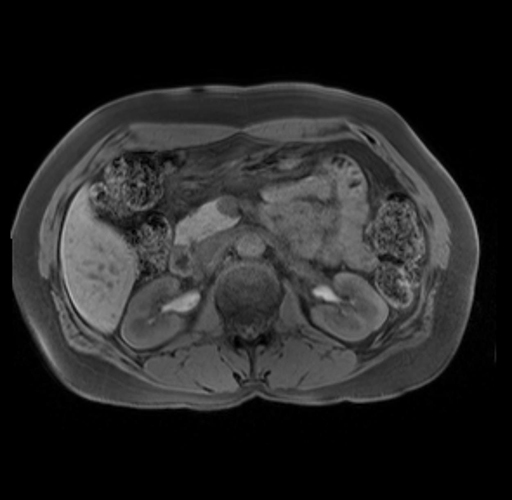

Imaging Analysis

Look through the patient's CT scan to identify any areas of concern for the necessary procedure.

Based on your CT findings, which issue(s) are present and would give reason for "planned slowing down moment(s)" in this case?